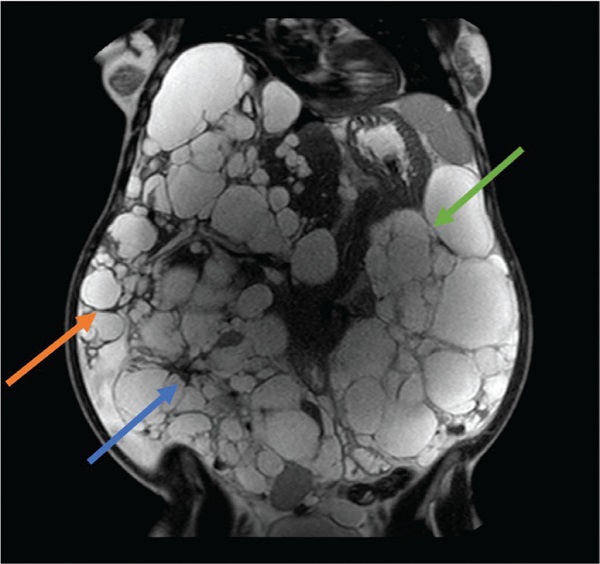

Alla luce di quanto discusso finora e delle evidenze scientifiche disponibili, possiamo ora cercare di sviluppare un approccio terapeutico mirato che tenga conto delle esigenze cliniche specifiche delle donne affette da ADPKD, con l’obiettivo di massimizzare i benefici e di ridurre al minimo i potenziali rischi (Fig. 1).

FIGURA 1 - Donna di 41 anni affetta da ADPKD, con nefro- ed epatomegalia. In anamnesi: 5 anni di terapia contraccettiva a base di estroprogenistico e 2 pregresse gravidanze. Classe Mayo 1 E.

Freccia arancione: margine inferiore del lobo epatico destro; freccia blu: rene destro; freccia verde: rene sinistro.